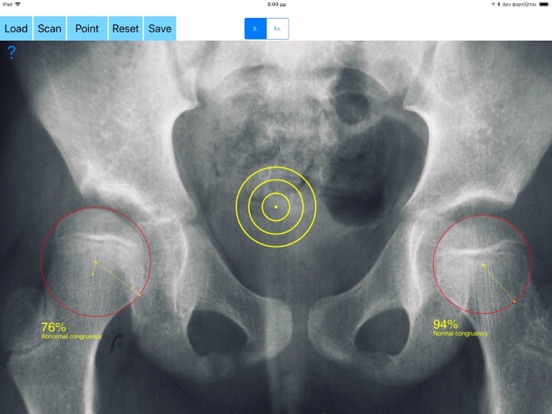

Congruence is present when the center of the femoral head (ball) and that of the acetabulum (socket) coincide. Lack of hip congruence between the femoral head and the acetabulum leads to increased local contact stresses, degeneration and consequently to premature arthritis. Although corrective hip osteotomies for the realignment of the dysplastic acetabulum is the main goal of treatment strategies, if the joint space congruency remain fair this end up in failure. Joint congruency can be rated subjectively according to the surgeons experience but according to international literature, evaluation and monitoring hip joint congruency is crucial to judge and predict the outcome of treatment. The App measures objectively the congruence and gives values as percentage (Congruence Index) which can be used for evaluation or comparisons of treatments modalities like acetabular osteotomies in developmental dysplasia or Legg-Calve-Perthes disease of the hip.

-Offers a very convenient and most accurate possibly way to determine joint space congruency with two methods. With transparent circular template-Moses template- you try to find the best-fitted circle superimposed over the femoral head, you mark the femoral head center and with the same manner you locate the acetabular center of the weight bearing zone. When the center of the best-fitted circle of the acetabulum coincide with the center of the femoral head, the concruency of the joint is considered normal (CnI =100%).The app calculates automatically the congruency index. The results are printed as a percentage of congruency of the hip joint and the hip is categorized as normal or abnormal.